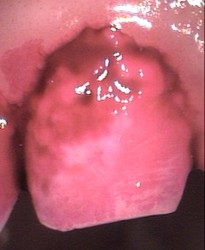

Frenectomy 2 pre-op lateral Frenectomy 3 immediate post-op

Frenectomy 4 immediate post-op close-up